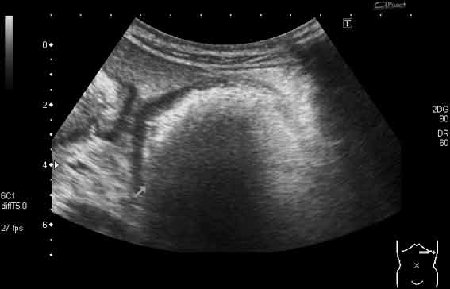

УЗИ, трихобезоар желудка. Gastric trichobesoar, ultrasonography.

Наблюдение наших коллег, работающих в педиатрии (valeriy.andilevko).

УЗИ, девочка 8 лет с ментальными расстройствами.